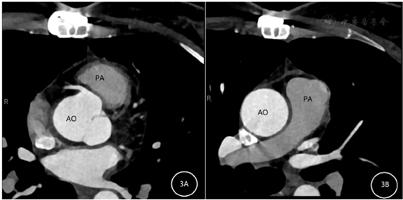

患者术后心电图无缺血变化。手术后患者的疼痛症状消失,出院时无重大并发症。术后5个月,复查冠状动脉三维成像结果(图3)冠状动脉、肺动脉未见分流,冠状动脉无明显狭窄。心脏彩超提示:EF 63%,冠状动脉-肺动脉瘘术后,三尖瓣轻度反流,左心功能正常。术后定期随访未见不适症状。

我们的病例极为罕见,因为大多数报道的病例是冠状动脉前降支(left anterior descending,LAD)和肺动脉之间的瘘管,但在本案例中,肺动脉与左右冠状动脉形成多条瘘管,并且表现为心绞痛症状,患者经手术治疗后症状明显缓解,术后5个月复查冠状动脉CTA未见冠状动脉-肺动脉瘘。在表现为心绞痛的患者中,冠状动脉造影可提供冠状动脉狭窄程度、解剖位置、瘘管和动脉瘤等信息,还有助于进行适当的手术评估。由于CPAF在临床上罕见,在表现心绞痛和劳累后呼吸困难的患者中容易被忽略,因此在这类患者中更应该明确疾病的原因,不能忽略类似的少见或罕见的疾病,以免造成漏诊。